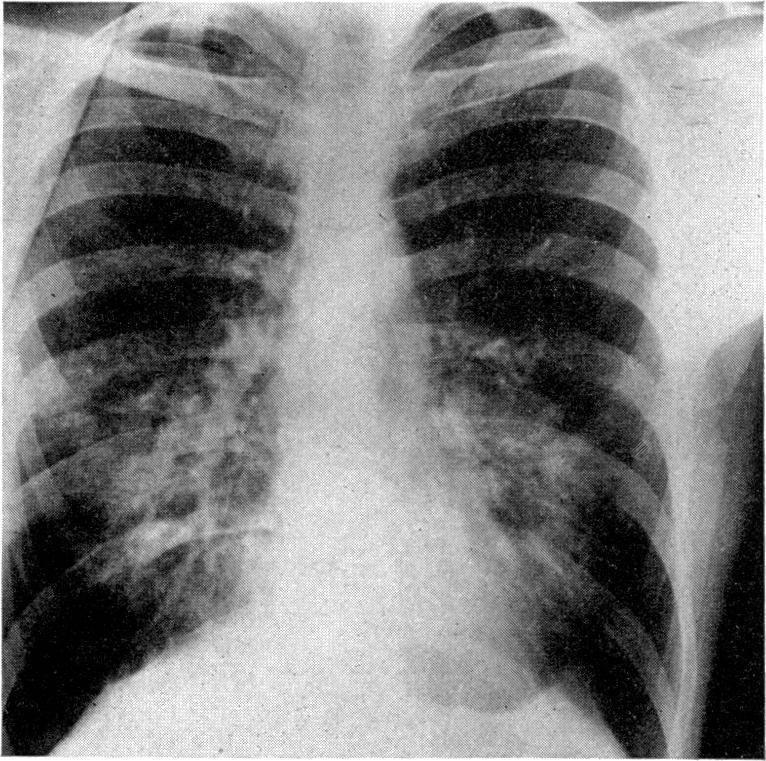

The immunoglobulin class and subclass of cytophilic antibodies have been studied using peripheral leucocytes from twenty-two patients with allergic bronchopulmonary aspergillosis, aspergilloma and cryptogenic pulmonary eosinophilia. In patients with allergic bronchopulmonary aspergillosis, significantly increased histamine liberation occurred following challenge of their leucocytes with antisera to IgE, IgG2, IgG3 and IgG4 as well as with Aspergillus fumigatus antigen. The results were considerably modified if the patient was receiving corticosteroids at the time of the test. The presence of IgG2-specific antibody to A. fumigatus in the serum of one patient, capable of sensitizing donor leucocytes, was demonstrated in passive sensitization experiments. In two patients with uncomplicated aspergillomas no evidence of cytophilic antibody to any class was found although large amounts of precipitating IgG antibody was present in the serum. Two patients with aspergilloma and systemic symptoms of weight loss and fatigue (which have been interpreted by others as 'hypersensitivity' responses) had increased amounts of cytophilic antibody similar to those with allergic bronchopulmonary aspergillosis. Six patients with cryptogenic pulmonary eosinophilia were also studied. No evidence of specific antibody to A. fumigatus was found but, as a group, significantly increased histamine liberation using antisera to IgG2 was demonstrated. Individual patients also showed evidence of other classes of cytophilic antibody, one having IgE, three IgG3 and two IgG4. The relationship between heat-stable short-term sensitizing antibody (IgG STS) inducing immediate skin responses and the pattern of cytophilic antibodies found in our patients with bronchopulmonary aspergillosis having dual (immediate and late reactions) is discussed. Clinically these tests are of diagnostic value and they may be helpful in assessing symptomatic patients with aspergillomas for corticosteroid treatment.